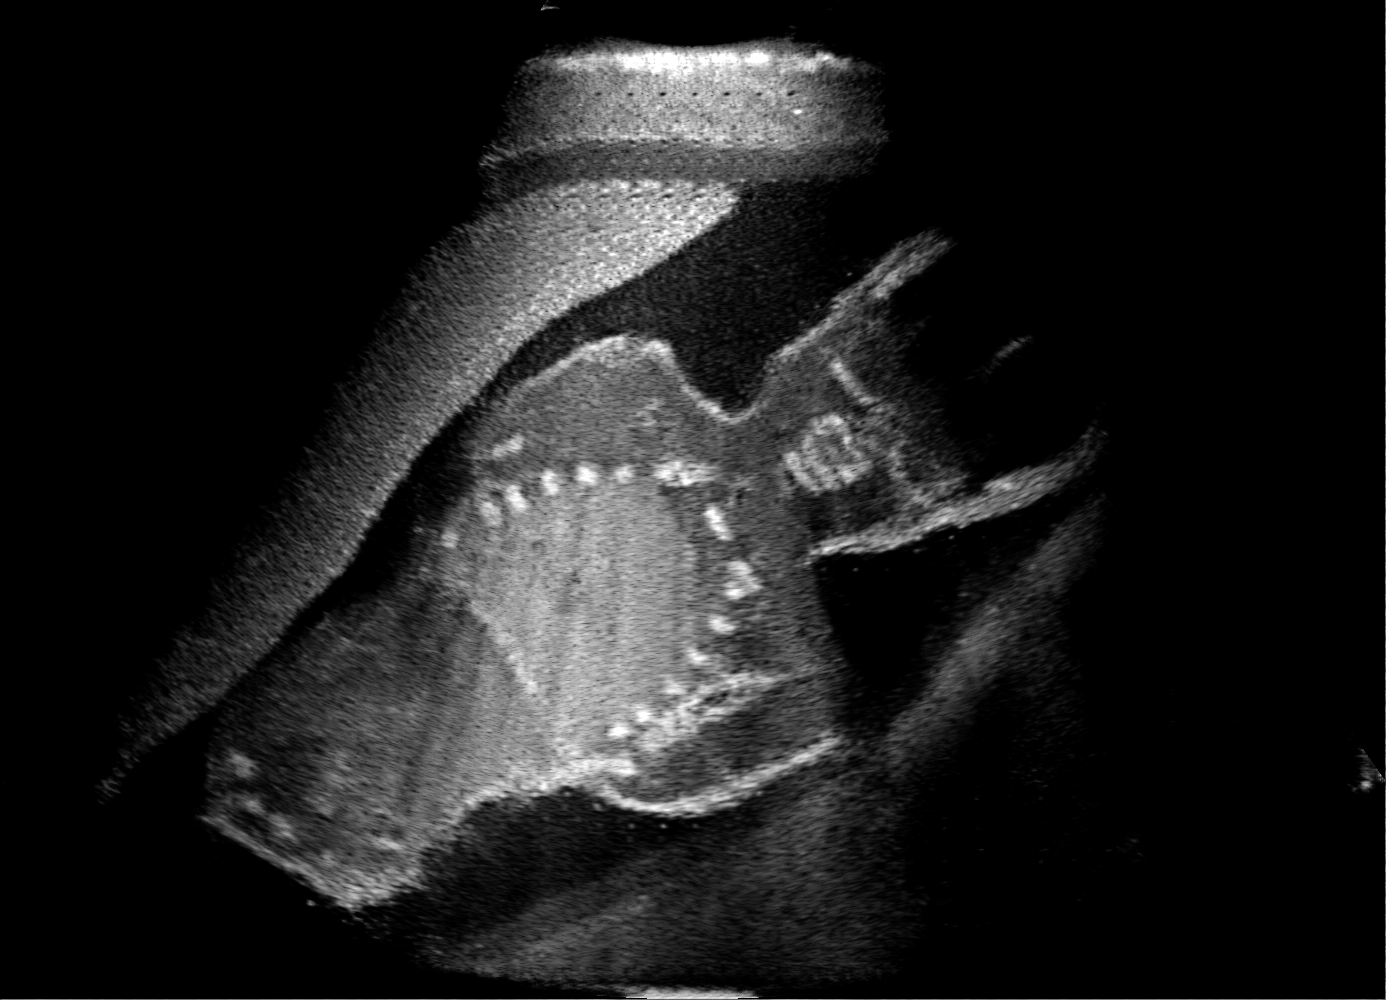

Qualitative evaluation.

Fig. 2 depicts the qualitative results for all the models mentioned above, with arrows pointing at structures relevant to discussion points below. The visual results of the ablated variants of SA2H show substantial quality degradation compared to the full SA2H model, demonstrating the importance of each proposed architectural contribution. Given only segmentation map in the network input, SA2H-att fails to generate acoustic shadows, e.g. those cast by the ribs. Detailed structures such as the cervical vertebrae are blurred out in the SA2H-concat results, which also contain hallucinated structures mainly due to insufficient preservation of input information along the encoding-decoding path. With SA2H-conv, checkerboard artefacts are observed due to the lack of proposed additional stride-1 convolutional layers. SA2H-noise without any explicit noise input is seen to be sub-optimal at generating textural details. The baseline method NSA2H fails to preserve anatomical structures and acoustic shadows in all cases, while the simulated textures also show significant artefacts such as checkerboard patterns. Realism of different simulation aspects may become relevant given different clinical applications and scenarios. For instance, improved structural preservation, e.g. with the hyperechoic bony structures such as the skull and the ribs, of the final model over its ablated variants and NSA2H may prove relevant in fetal head measurements, while the textural improvements facilitating screening fetal organ maturity, e.g. lungs. Compared to the silver-standard model LSA2H with a low-quality rendered image as additional input, SA2H is seen to be on par in structural preservation. Note that shadowing on homogenous regions (e.g. the rib shadowing on the homogenous lung region on the 4th column of Fig. 2) with our proposed method SA2H is represented more faithfully compared to LSA2H, whereas shadows on structurally complex regions (e.g. the skull shadowing around the heart and surrounding tissues on the 3rd column of Fig. 2) are suboptimal with our SA2H. Therefore, one may have to evaluate our method given particular simulation tasks, e.g. its clinical validity for fetal heart exams. However, even with low quality rendered images, LSA2H leads to artificial enhancements of intensities, lack of acoustic shadows, and low-quality textures especially near the probe, for which SA2H yields satisfactory results as illustrated in Fig. 2.

(a) Target

(b) SA2H

(c) SA2H-att

(d) SA2H-concat

(e) SA2H-conv

(f) SA2H-noise

(g) NSA2H

(h) LSA2H